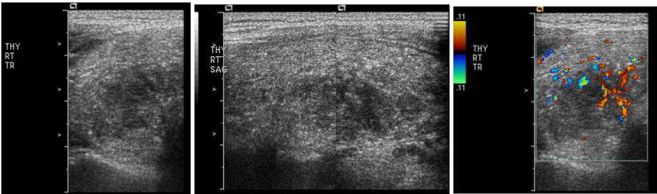

37.一位46歲女性因為常常頭暈,爬樓梯時感到很喘而來醫院求診。身體檢查除臉⾊與結膜蒼白之外,並無其他 明顯異常。患者血壓106/76 mmHg,脈搏每分鐘72次,規則心跳,無發燒,亦無體重減輕或是食慾降低的現 象。血液數據顯示血紅素7.6 g/dL,白血球4,030/μL,無異常分類,血小板418,000/μL,MCV 74.8 fL(參考 區間80~100),ferritin 3.84 ng/mL(參考區間28~365),serum iron 10 μg/dL(參考區間51~209), TIBC(total iron binding capacity)459 μg/dL(參考區間268~593)。血液抹片如下圖所示。有關這位病人 最可能的疾病之描述,下列何者錯誤?

(A)此類病人的血液中的reticulocyte counts常是降低的 (B)此類病人的骨髓中的sideroblast比例常是降低的 (C)此類病人的紅血球中的protoporphyrin 量常是降低的 (D)此類病人的red cell distribution width(RDW)index常是增加的